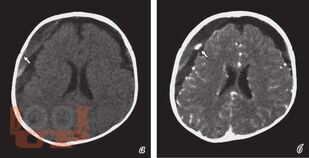

Учебное пособие посвящено вопросам организации и проведения нейровизуализационной диагностики у детей при энцефалитах и менингитах на различных этапах заболевания. В книге указаны особенности визуализации энцефалитов в зависимости от этиологии и тяжести течения заболевания.

Мы приводим разбор возможностей диагностических методик и усовершенствованный алгоритм нейровизуализационной диагностики при нейроинфекциях у детей.